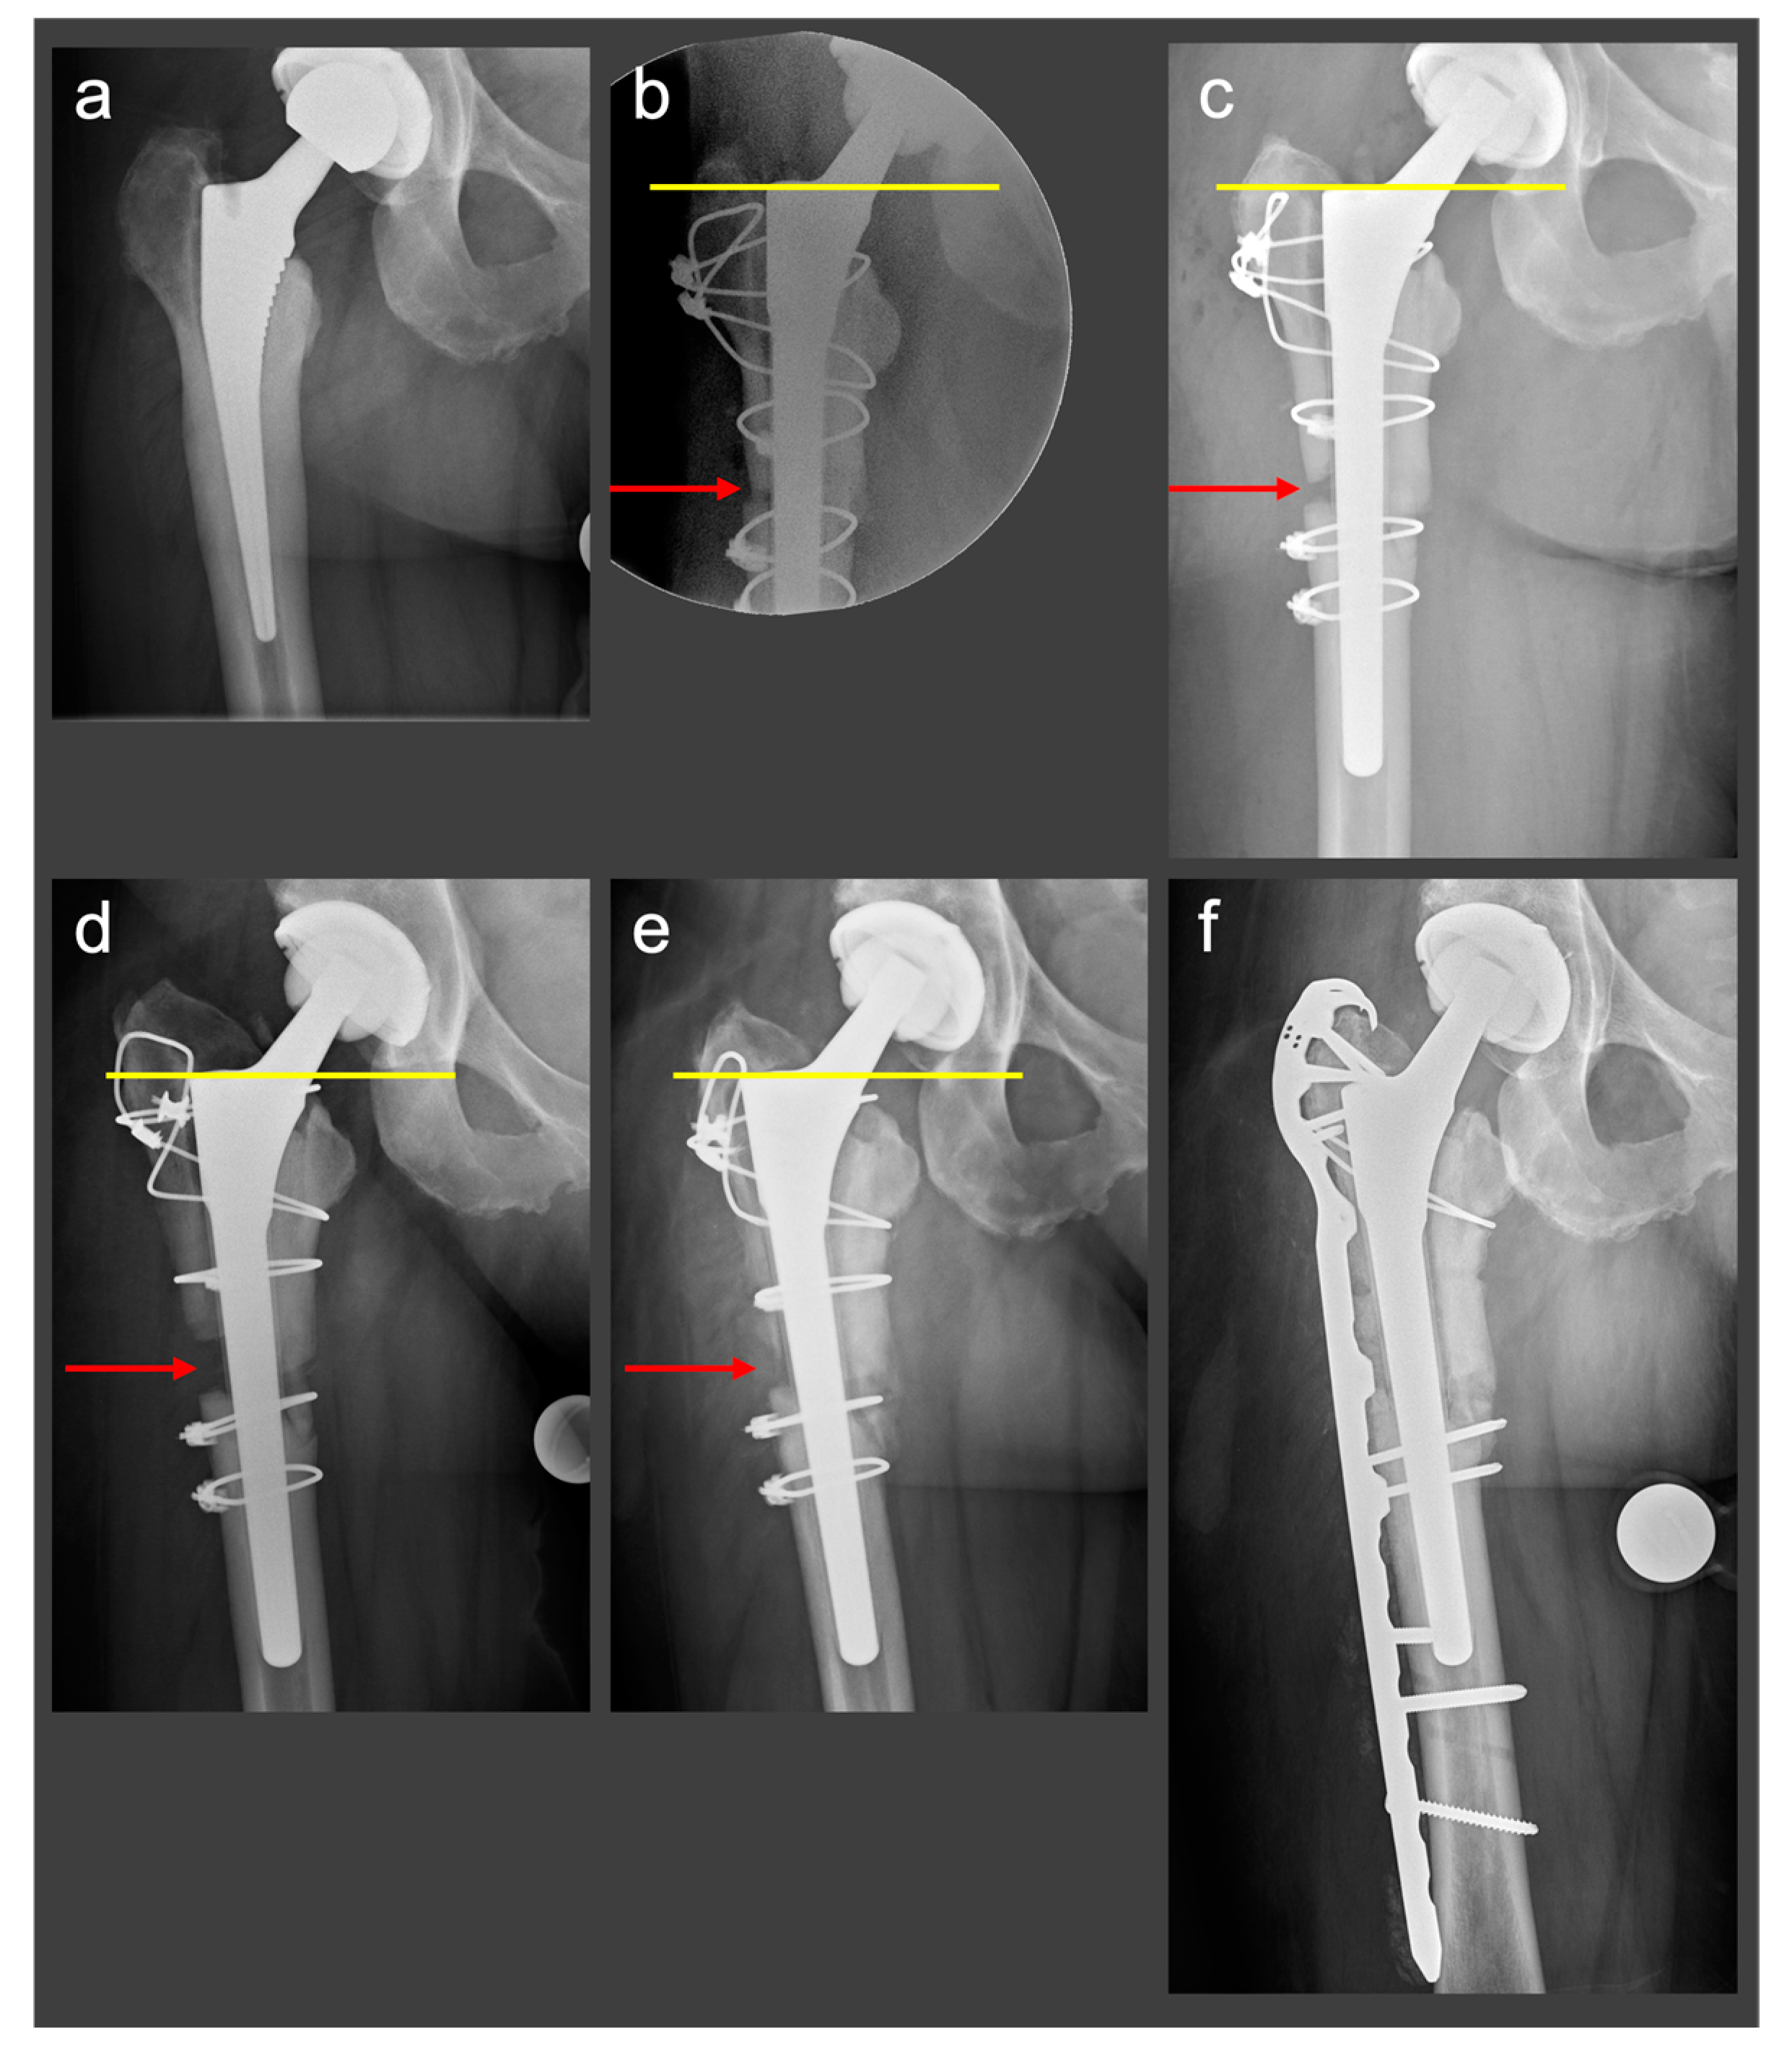

2.2.2. Clinical Case

2.3. Novel Surgical Technique: A Monocortical Screw for Preventing Trochanteric Escape

2.3.1. The Surgical Technique

2.3.2. Biomechanical Principles

2.3.3. Clinical Case